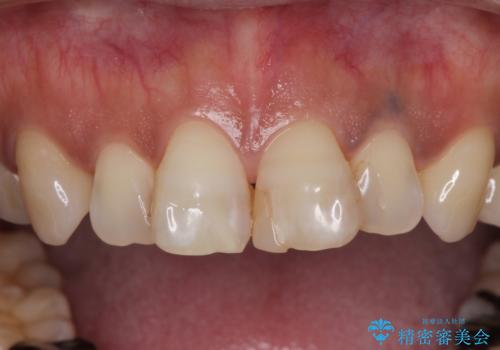

- 何度もコンポジットレジンによる修復を繰り返した結果、冷たいものがしみるようになってしまったとのことで来院された患者様です。

前歯2本が捻れている形態も気になるとのことであったので、虫歯の治療を兼ねて、オールセラミッククラウンにて補綴治療を行うこととしました。

2本とも治療前の歯髄の状態は正常でしたが、補綴治療により歯を大きく削ることになるため、歯髄が炎症を起こすリスクがあることを了解いただきました。